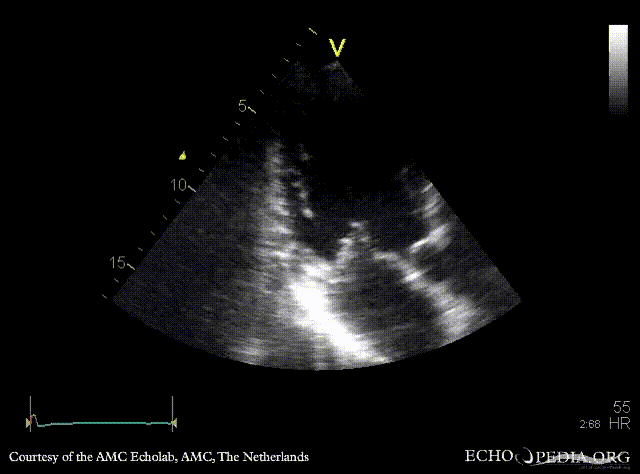

M-Mode through left ventricle, dilated LV